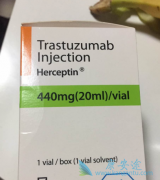

HER 2与非小细胞肺癌中的EGFR和ALK一样,都是一些肿瘤的驱动基因。HER 2阳性通常见于乳腺癌和胃癌,作为一种癌症的分子分型指导治疗。另外,一些EGFR突变的非小细胞肺癌患者对EGFR-TKI治疗耐药,也有HER 2的原因,这里暂且不谈。 抗HER-2治疗一直以 ...

吡咯替尼 是新一代泛-ErbB受体酪氨酸激酶抑制剂,作为一款靶向药,靶点涵盖EGFR和HER 2,但主要定位还是抗HER 2靶向药。相同靶点最有代表性的药物就是曲妥珠单抗(原研药物商品名为赫赛汀),这里解答一个疑问:为什么同是HER 2靶向药,一个是“XX替尼 ...